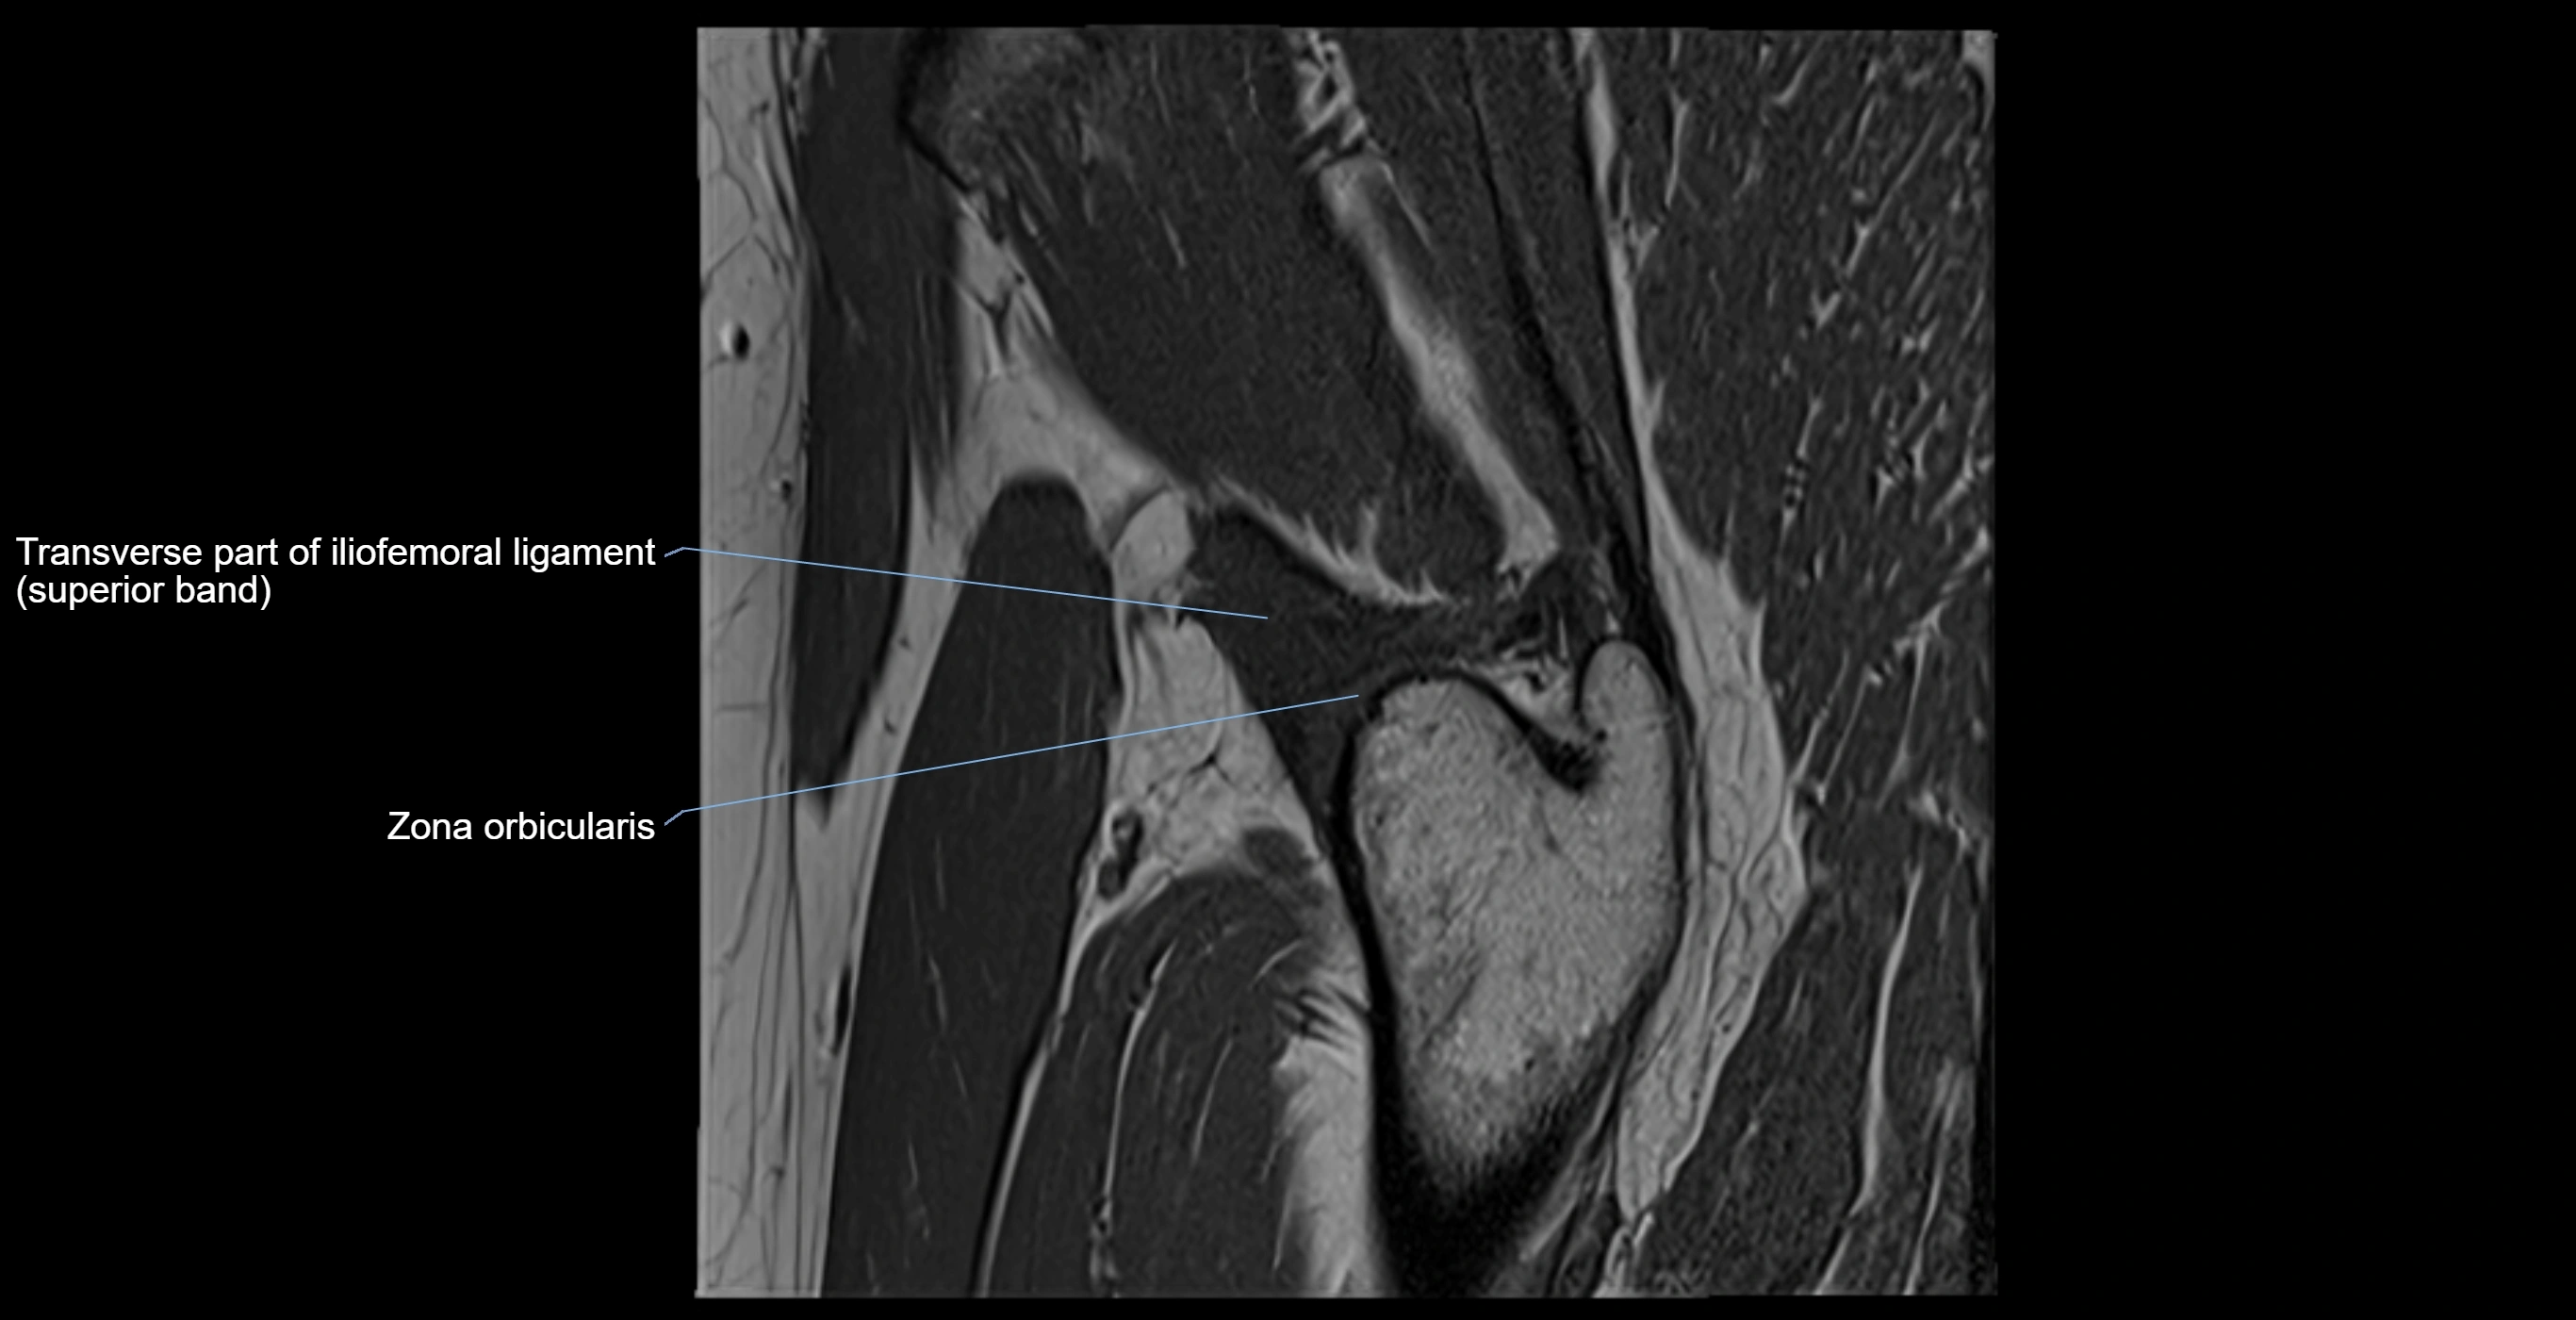

MRI Appearance

T1-weighted images:

• Labrum: low signal intensity (dark)

• Surrounded by intermediate signal joint fluid (bright on arthrogram)

• Tears: linear or focal areas of intermediate-to-high signal interrupting labral continuity

T2-weighted images:

• Joint fluid: bright, making labral tears visible as fluid extending into or around labrum

• Degeneration: may show areas of increased signal within labrum

MRI image

image